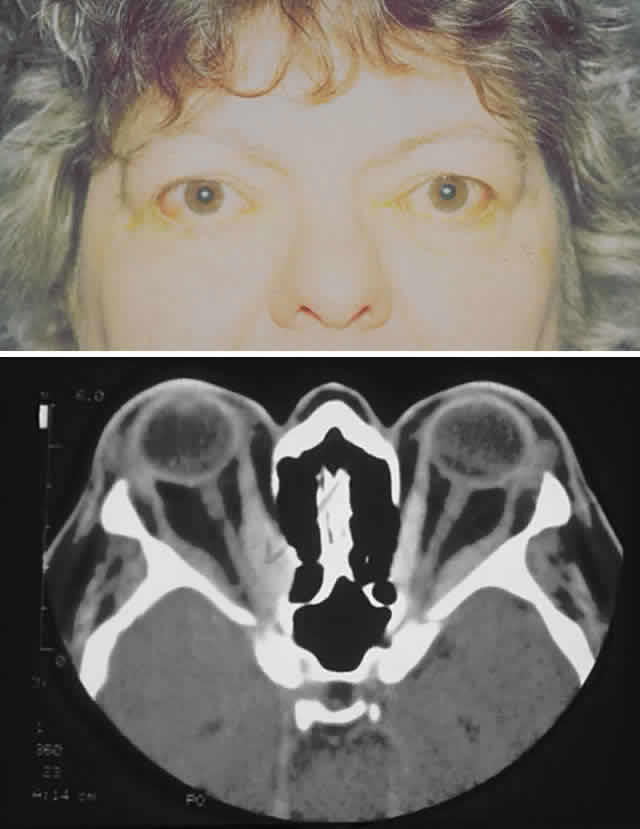

Dysthyroid orbitopathy (DO), also known as thyroid-associated orbitopathy (TAO) or Graves' disease, is the most common orbital disorder in adults.1,2 The diagnosis of this disease is discussed elsewhere in these volumes. Morbidity from this disease occurs from exposure keratopathy, extraocular myopathy, optic neuropathy, and disfigurement (Fig. 1). When medical therapies fail or when they are not expected to benefit the patient sufficiently, surgery may be indicated. As a general rule, surgery during the active phase of Graves' disease is not performed except for vision-threatening disorders (e.g., optic neuropathy or severe exposure keratopathy).

Fig. 1. A 59-year-old woman with severe dysthyroid orbitopathy including bilateral optic neuropathy, left lid retraction with corneal exposure, extraocular myopathy, and disfigurement.